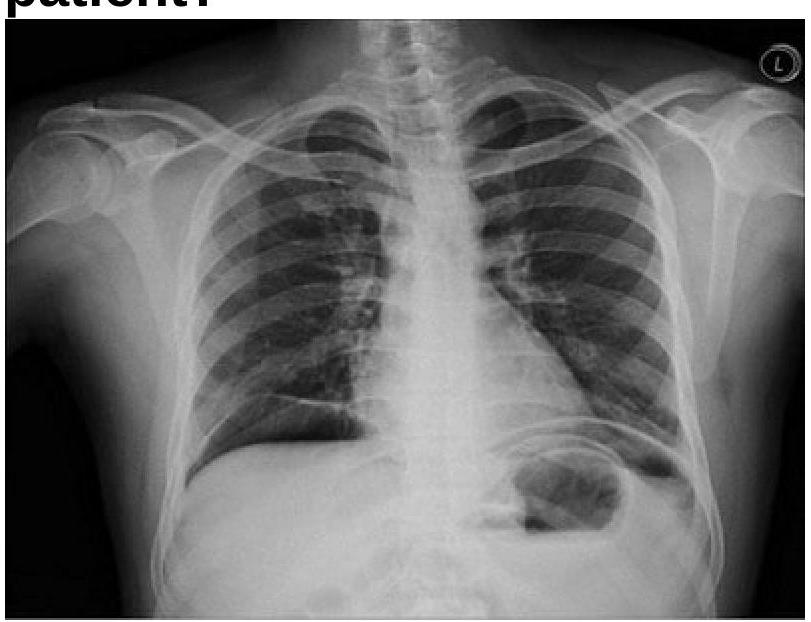

A 40 years old male was brought emergency with severe abdominal pain. On examination, pulse rate was 112/minute and systolic BP was 80 mmHg. Chest x-ray is given below. What is the most appropriate management?

Question 7: A 40 years old male was brought emergency with severe abdominal pain. On examination, pulse rate was 112/minute and systolic BP was 80 mmHg. Chest x-ray is given below. What is the most appropriate management?

- A. Exploratory laparotomy (Correct Answer)

Explanation: ***Exploratory laparotomy*** - The chest x-ray shows **pneumoperitoneum (air under the diaphragm)**, which, combined with severe abdominal pain, tachycardia, and hypotension (signs of **septic shock**), is highly indicative of a **perforated viscus**. - **Emergency exploratory laparotomy** is the definitive treatment to identify and repair the perforation, control contamination, and prevent further deterioration. *Saline wash of stomach* - This procedure is typically used for gastric lavage in cases of **poisoning or drug overdose**, or to clear the stomach in preparation for endoscopy. - It does not address a viscus perforation or the widespread abdominal contamination and systemic septic response seen in this patient. *Intercostal tube drainage* - **Intercostal tube drainage** (chest tube placement) is used to drain air (pneumothorax) or fluid (pleural effusion, hemothorax, empyema) from the pleural space, not the abdominal cavity. - While there is air visible on the x-ray, it is **subdiaphragmatic (pneumoperitoneum)**, not within the pleural space, and thus a chest tube would be ineffective and inappropriate. *IV antibiotics* - **Intravenous antibiotics** are crucial for managing sepsis associated with a perforated viscus and should be administered promptly. - However, antibiotics alone are **not sufficient** to treat the underlying mechanical problem of a perforation, which requires surgical repair to prevent ongoing bacterial contamination and sepsis.